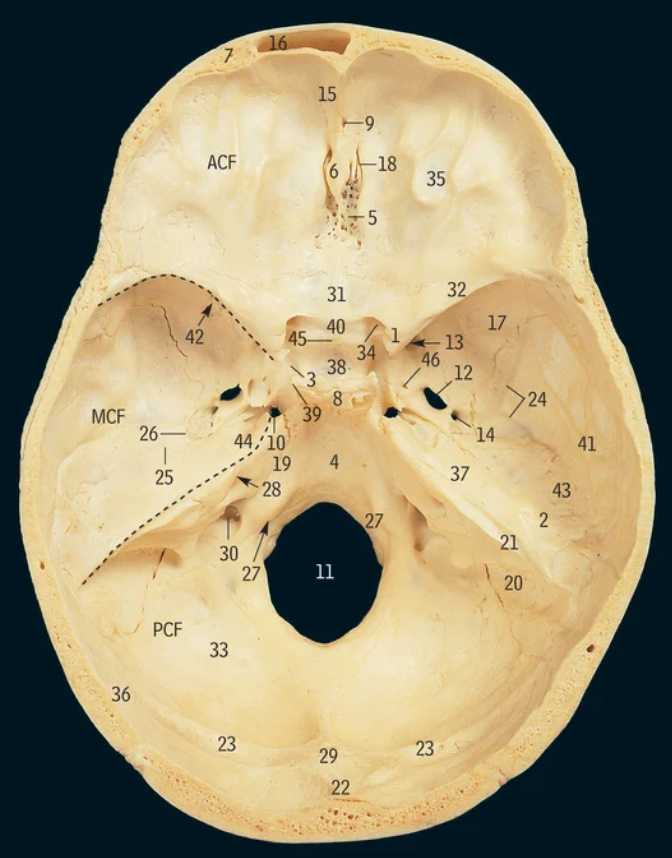

5

Cribiform plate

6

Crista galli

17

Greater wing of sphenoid bone

32

Lesser wing of sphenoid bone

38

Pituitary fossa

34

Optic canal

42

Superior orbital fissure

12

Foramen ovale

13

Foramen rotundum

14

Foramen spinosum

27

Hypoglossal canal

11

Foramen magnum

Which part of the ethmoid bone does the olfactory nerve exit

Which part of the ethmoid bone does the falx cerebri attach

What cranial nerves travel through the superior orbital fissure

CN III/3, IV/4, V1/ophthalmic, VI/6

What travels through the hypoglossal canal

Hypoglossal nerve

What travels through the formen magnum

Spinal cord, accessory nerve